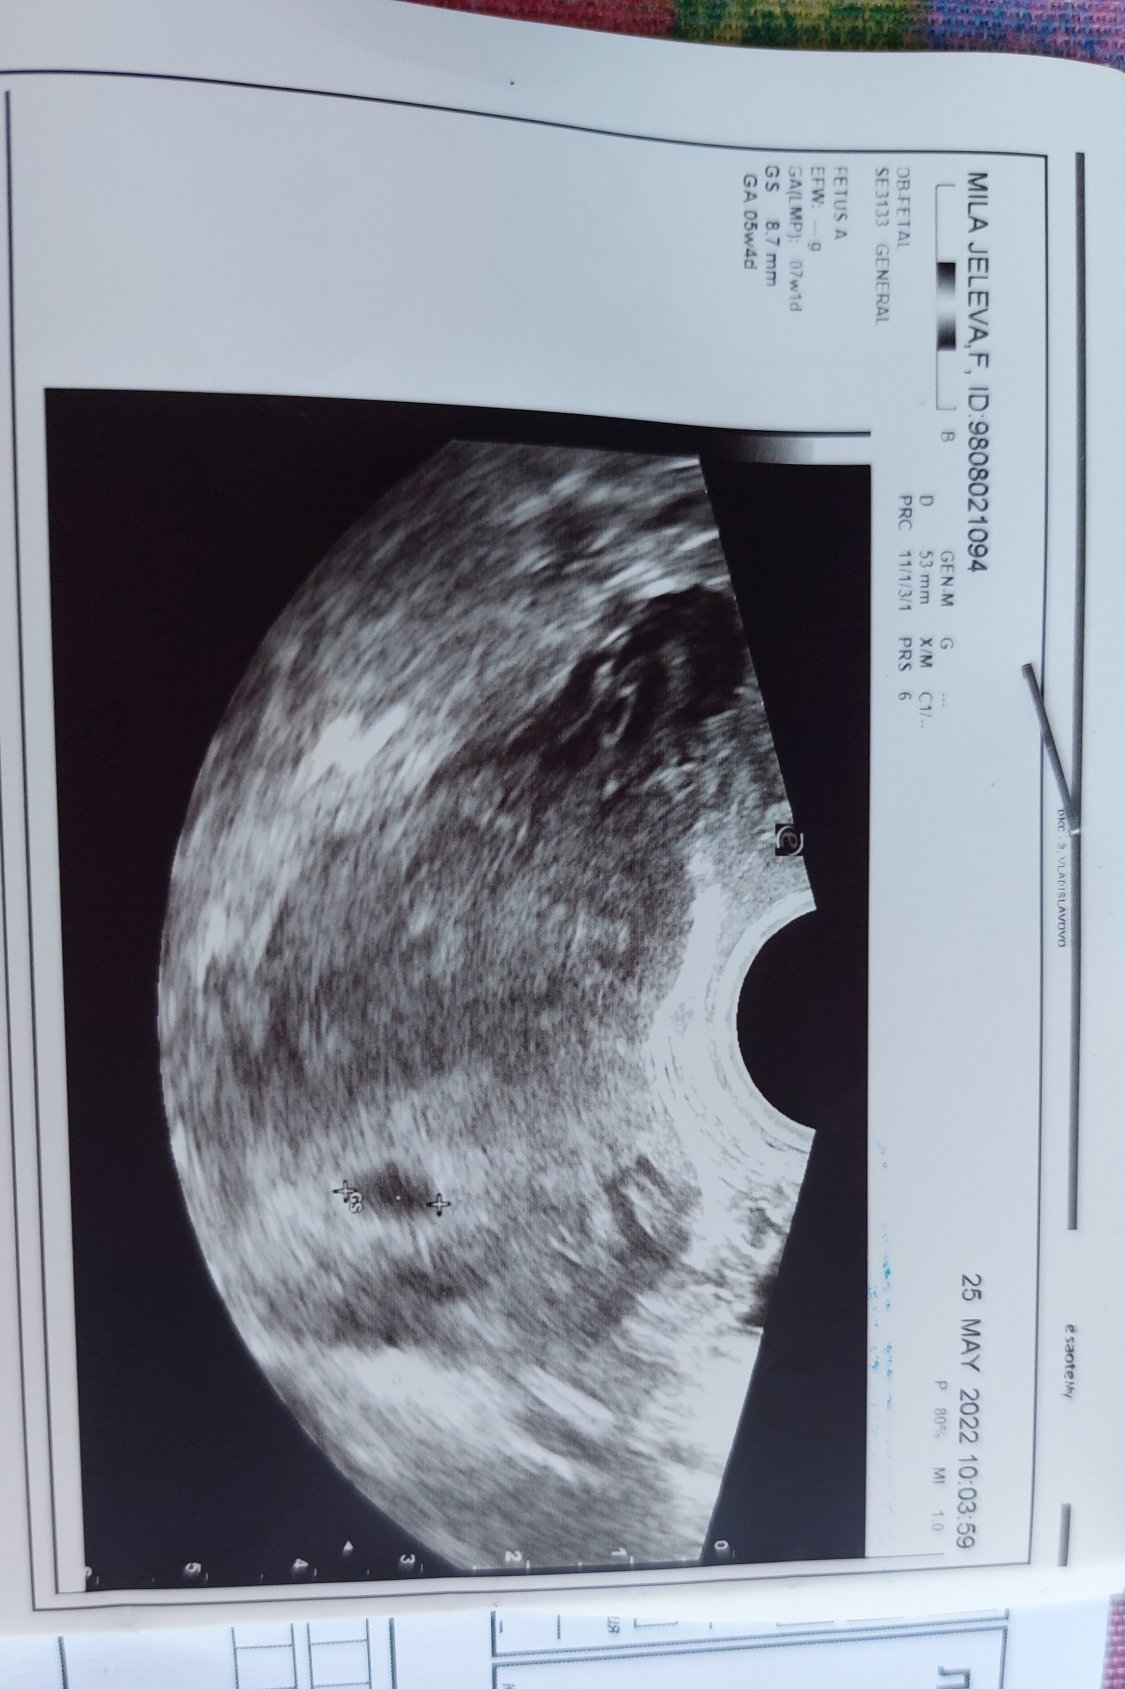

2ра бременност ми е! Трябва да отговарям на 7г.с,но по измерване съм в 5г.с.

Първата ми бременност също беше с 2 седмици назад - обясниха ми,че имам по-късна овулация.

По ПРМ сте 7+1 , по УЗИ 5+4 . Според мен е рано да се каже категорично , но зацапването във вашия случай е по-притеснително . Дано ЧХГ се покачва нормално и бременността се задържи .